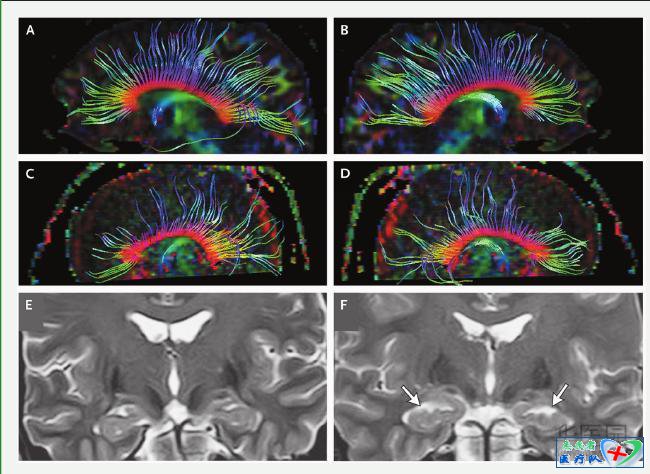

患者一氧化碳中毒后的脑磁共振成像(MRI)检查(为了研究目的而实施,某些病例有施行MRI的临床适应证,例如为了除外与一氧化碳暴露无关的疾病),有可能显示异常结果(图3)。在一项纳入一氧化碳中毒患者的前瞻性研究中,脑MRI显示(患者的)T2加权高信号数,多于基准数据库中的高信号数。虽然影像学异常改变的发生率还不知道,但其他纳入一氧化碳中毒患者的研究曾经报告过中毒数年后的基底神经节病变、海马和其他结构萎缩,以及中毒1个月后扩散张量成像的异常结果。然而,这些异常对一氧化碳中毒而言都不具有特异性。